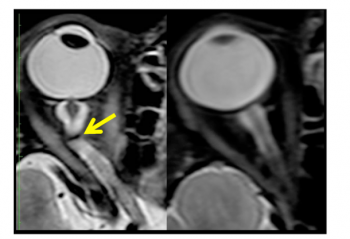

Pre and Post flight MRI are indicated. MRI imaging may show increases to optic nerves sheath diameter and optic nerve diameter with “kinks” to the optic nerve visible as T2 hyper intensities (96%).[18][3]Posterior globe flattening and pituitary dome concavity with posterior stalk deviation were also seen within the microgravity exposure cohorts.[18] Cephalad brain shift has also been demonstrated on post flight MRI.

Lumbar puncture along with MRI have also been used to assess SANS but are limited to terrestrial use. Evaluation of SANS with MRI may show flattening of posterior globes, distended optic nerve sheaths, tortuous optic nerves and papilledema.[2] Lumbar punctures performed in the context of SANS typically demonstrate normal to borderline increased opening CSF pressures which have been documented as high as 28.5 cmH20 at 2 months after landing.[2] Lumbar puncture and MRI have also been used to assess SANS but are limited to terrestrial use. Evaluation of SANS with MRI may show flattening of posterior globes, distended optic nerve sheaths, tortuous optic nerves and papilledema.[2] Lumbar punctures performed in the context of SANS typically demonstrate normal to borderline increased opening CSF pressures which have been documented as high as 28.5 cmH20 at 2 months after landing.[2]. Remote ultrasound-guided lumbar puncture may prove beneficial and safe while in flight.[19] Many of these findings bear a similarity to terrestrial IIH; however, the findings in SANS frequently present asymmetrically[2] which is uncommon for IIH.[20]